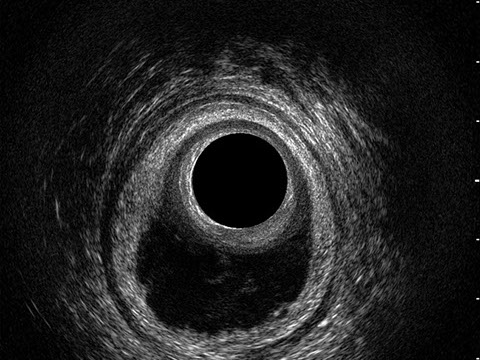

L’ecografia transanale è un esame diagnostico per immagini che consiste nell’introduzione di un trasduttore ad ultrasuoni. Le immagini qualitativamente migliori del canale anale sono ottenute usando un trasduttore rotante, montato in un manipolo rigido, che fornisce un’immagine a 360°. Con le apparecchiature più moderne è anche possibile ottenere immagini tridimensionali.

L’ecografia transanale permette di distinguere la sottomucosa che riveste il canale anale, lo sfintere anale interno, e lo sfintere anale esterno.

Le principali indicazioni all’esecuzione di tale esame sono lo studio dell’integrità delle strutture muscolari nei casi di incontinenza fecale, lo studio topografico dei processi settici perianali (ascessi e fistole) e lo studio dei processi proliferativi epiteliali (carcinoma anale).